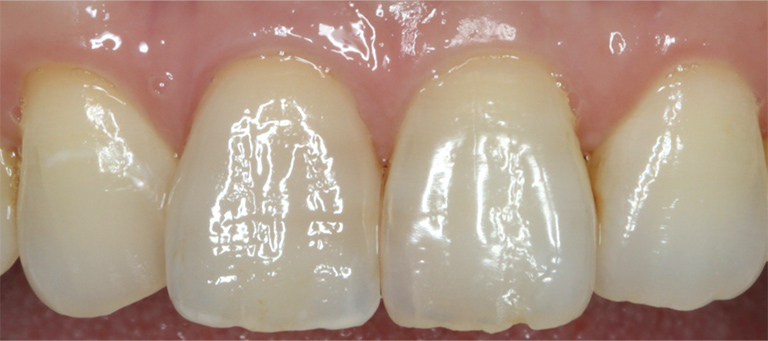

前歯を綺麗にしたい

- 相談内容

- 前歯を綺麗にしたい

- 患者情報

- 40代男性

- 来院時悩み

- 特になし

- 治療前の状態

- 空隙歯列(すきっぱ)、歯牙形態の不整

- 治療内容

- ホワイトニング・ラミネートベニア

- 治療期間

- 4ヶ月

- 治療費用

- オフィスホワイトニング ラミネートベニア 4本

【治療のリスク・注意点】

定期検診で噛み合わせをチェックする必要があり、調整を行うこともあります。噛み合わせの調整に費用はかかりません。メンテナンスが甘い場合、セラミックが欠けたり破損したりすることがあります。

ホワイトニングはほとんどの方が歯を白く明るく変化させることができますが、ごく稀にあまり変化が見られない場合もあります。この方は問題ありませんでした。